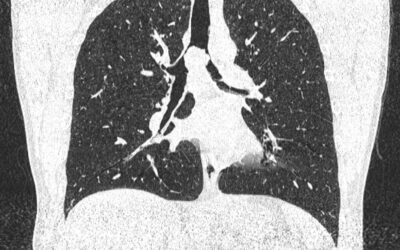

ფილტვის მოცულობის ბრონქოსკოპიული შემცირება ბულოზური ემფიზემის შემთხვევაში

პაციენტი 42 წ მამაკაცი. აქტიური მწეველი. თავს ავად გრძნობს რამოდენიმე თვეა. ჩივილები: ძლიერი ქოშინი ფიზიკურ დატვირთვაზე, ჰაერის უკმარისობა, საერთო სისუსტე. გულმკერდის კტ კვლევით - ორივე ფილტვის ზედა წილებში გაიშვიათებული ფილტვის ქსოვილი, გიგანტური ბულები 10-14 სმ...